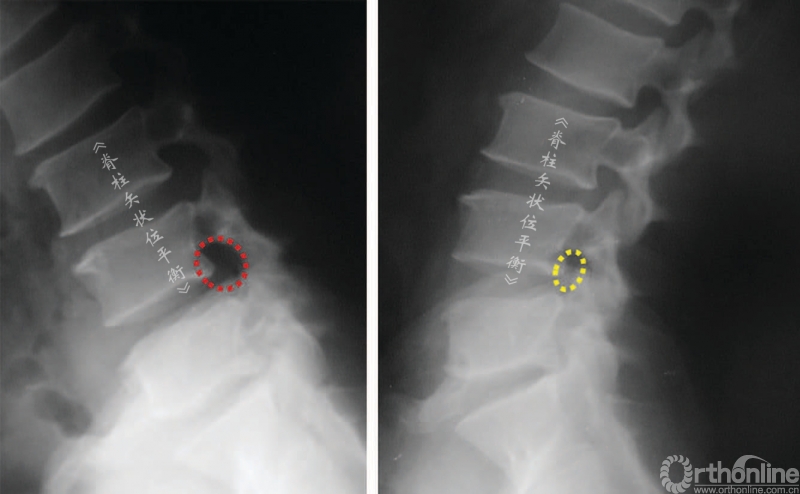

骨关节炎性的椎管狭窄导致伸展时(或前凸)比屈曲时(或后凸)出现更多的症状。不考虑椎管水平因素时,椎管前后径伸展时减小,屈曲时增大。同时,根据神经根的运动原理,神经根屈曲时向椎体前方运动靠近椎体和椎间盘,伸展时向后运动靠近后方椎弓(图8,图9)。

这也解释了颈椎伸展时会加剧压迫性、骨关节炎的颈、臂部的疼痛症状,腰椎屈曲或后凸时可改善腰椎管狭窄引起的神经源性跛行。伸展站立位X线不注射或注射造影剂(脊髓造影术)可证明这种动态受压的过程(图9,图10)。

脊柱后凸会挤压神经引起相应的症状,多见于腰椎管狭窄症。间歇性跛行是继发于椎管狭窄的一种临床症状,在处于伸展位置时加重。一些矢状位失平衡患者可以通过简单的神经根减压术改善其平衡状态。

图8 神经根位移,屈曲(A) 和伸展(B)时椎管容积改变

图9 屈曲(A)和伸展(B)时椎间孔的比较

图10 L3~L4 和L4~L5中央椎管体积减小,伸展位(B)和屈曲位(A)的比较